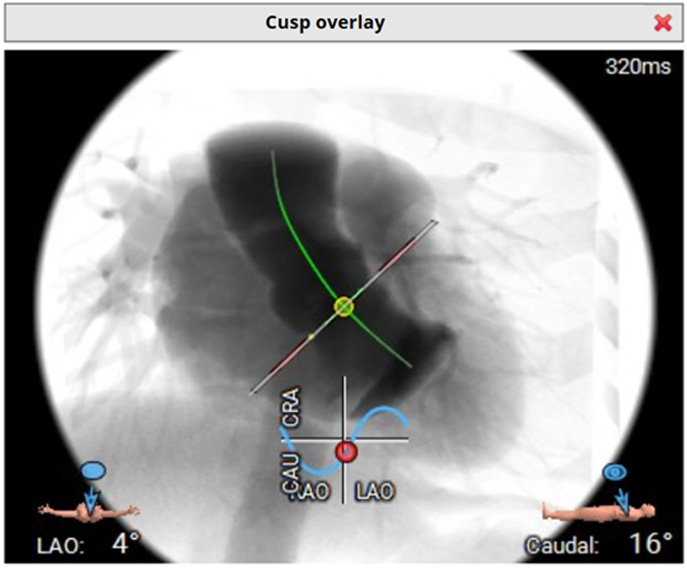

Computed tomography